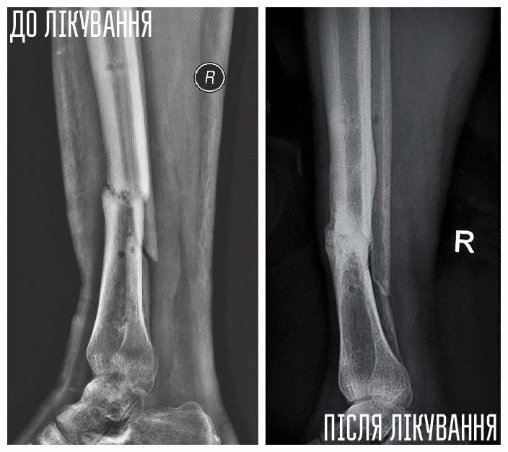

Юрій — боєць 51 ОМБр, травму отримав у липні 2014 року під Слов'янськом. Авто, яким кермував Юрій, підірвалося на ворожому фугасі, осколками тяжко травмувало руку і ногу хлопця. Юрія лікували у трьох шпиталях, та навіть за рік зусиль лікарів кістки гомілки не зрослися.У місці перелому почав формуватися несправжній суглоб, ногу тяжко викрутило — хлопець ледве пересувався навіть на милицях.

Влітку 2015 року, завдяки порадам та допомозі волонтерів, Юрій долучився до «Біотеху».